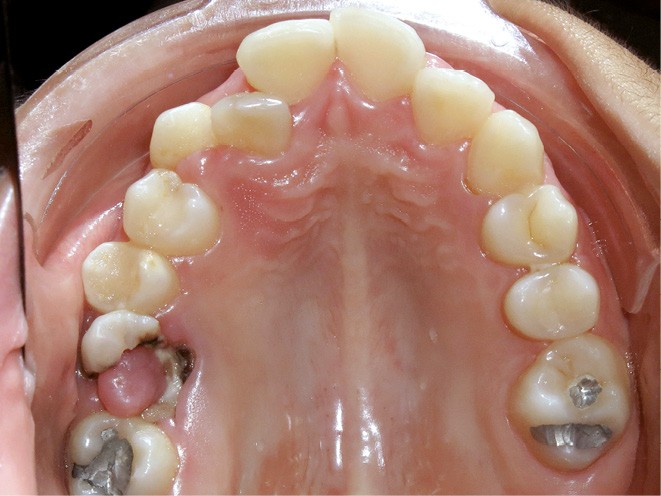

Le niveau d’hygiène est alarmant, car le rituel du brossage des dents n’est pas instauré dans la famille. Des caries se sont développées sur les dents temporaires et en ont imposé l’extraction. Les molaires permanentes ont dérivé mésialement, réduisant l’espace disponible sur l’arcade.

En denture adulte, la DDM est majeure avec un déficit de place estimé de 13 mm à la mandibule. Les lésions carieuses ont aussi touché les premières molaires permanentes maxillaires. La 26 a été avulsée et la 27 a pris sa place. Côté controlatéral, la 16 est fortement délabrée, rendant impossible sa conservation. Les molaires ayant plus mésialé à l’arcade mandibulaire, les rapports occlusaux sont de classe III. Les incisives sont versées vers l’avant, mais nous pouvons considérer qu‘il s’agit d’une biproalvéolie ethnique. Du point de vue squelettique, le patient présente une classe II squelettique par rétromandibulie sur un schéma facial hyperdivergent (fig. 1a-j).